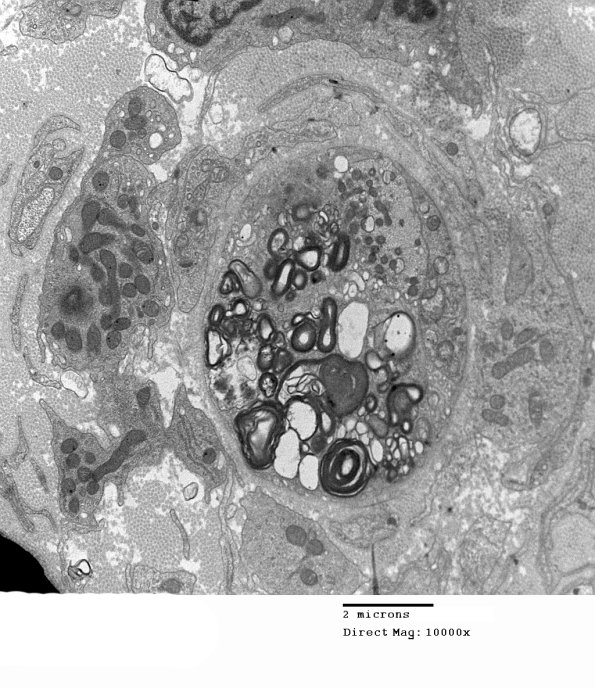

6C1A,B At first I thought this was a degenerating axon but higher magnification shows a preserved axon (arrow, 6C1B) (electron micrographs)